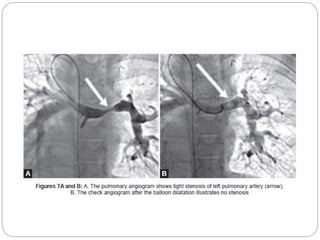

 Balloon dilatation of pulmonary stenosis

 Balloon dilatation and/or ductal stenting

 Balloon dilatation of peripheral pulmonary artery

stenosis with or without stenting

 The supravalvar pulmonic stenosis, if discrete, can be

relieved by balloon dilatation